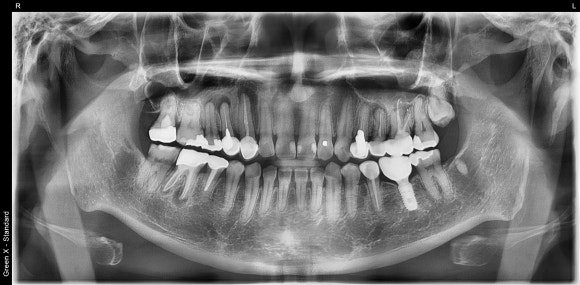

20250225

치료 후 찍은 치아들의 단체사진입니다.

엑스레이 상 염증이 보여 지켜보고 있는 치아들이 여럿 있습니다. 모쪼록 문제를 일으키지 않았으면 합니다^^;

이번엔 치료 받은 치아들도 오래 오래 쓰시길 희망해봅니다.